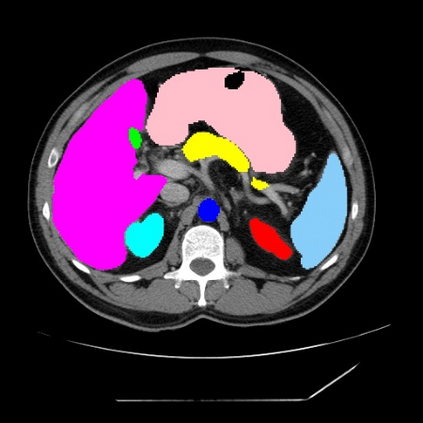

Integrating high-level semantically correlated contents and low-level anatomical features is of central importance in medical image segmentation. Towards this end, recent deep learning-based medical segmentation methods have shown great promise in better modeling such information. However, convolution operators for medical segmentation typically operate on regular grids, which inherently blur the high-frequency regions, i.e., boundary regions. In this work, we propose MORSE, a generic implicit neural rendering framework designed at an anatomical level to assist learning in medical image segmentation. Our method is motivated by the fact that implicit neural representation has been shown to be more effective in fitting complex signals and solving computer graphics problems than discrete grid-based representation. The core of our approach is to formulate medical image segmentation as a rendering problem in an end-to-end manner. Specifically, we continuously align the coarse segmentation prediction with the ambiguous coordinate-based point representations and aggregate these features to adaptively refine the boundary region. To parallelly optimize multi-scale pixel-level features, we leverage the idea from Mixture-of-Expert (MoE) to design and train our MORSE with a stochastic gating mechanism. Our experiments demonstrate that MORSE can work well with different medical segmentation backbones, consistently achieving competitive performance improvements in both 2D and 3D supervised medical segmentation methods. We also theoretically analyze the superiority of MORSE.

翻译:在医学图像分割中,整合高级语义相关的内容和低级解剖特征对于模拟这些信息非常重要。近期基于深度学习的医学分割方法已经显示出很有前景,可以更好地建模这些信息。然而,医学分割的卷积运算符通常在正则化网格上运作,这在本质上模糊了高频区域,即边界区域。我们在这项工作中提出了 MORSE,这是一个设计在解剖学水平上的通用隐式神经渲染框架,用于协助医学图像分割的学习。我们的方法的动机在于隐式神经表示已经被证明比离散化网格表示更有效地拟合复杂信号和解决计算机图形问题。我们方法的核心是将医学图像分割连续地对准粗糙的分割预测和模棱两可的基于坐标的点表示,并聚合这些特征来自适应地精细化边界区域。为了并行地优化多尺度像素级特征,我们借鉴了 Mixture-of-Expert (MoE) 的思想设计和训练我们的MORSE,使用随机门控机制。我们的实验表明MORSE可以很好地与不同的医学分割后骨干结合在一起,始终在2D和3D监督医学分割方法中实现了有竞争力的性能改进。我们还从理论上分析了MORSE的优越性。